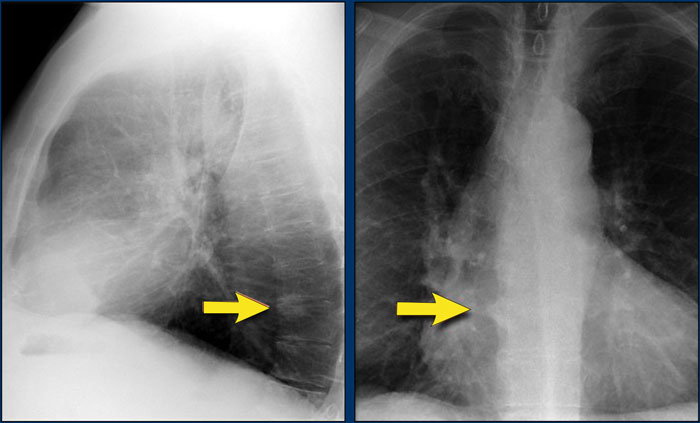

A key mediastinal–pulmonary interface to assess is the azygoesophageal recess (yellow arrow).

Azygo-esophageal recess

The azygoesophageal recess is located below the level of the azygos vein arch.

In this region, the medial aspect of the right lower lobe abuts the mediastinum between the heart anteriorly and the vertebral column posteriorly.

On its left, it is bordered by the esophagus.

Deviation of the azygoesophageal line may result from:

• Hiatal hernia

• Esophageal pathology

• Left atrial enlargement

• Subcarinal lymphadenopathy

• Bronchogenic cyst

On the PA chest radiograph, a lateral displacement of the azygoesophageal line can be seen.

It is caused by a hiatal hernia.

The arrow points to the barium contrast within the hiatal hernia.